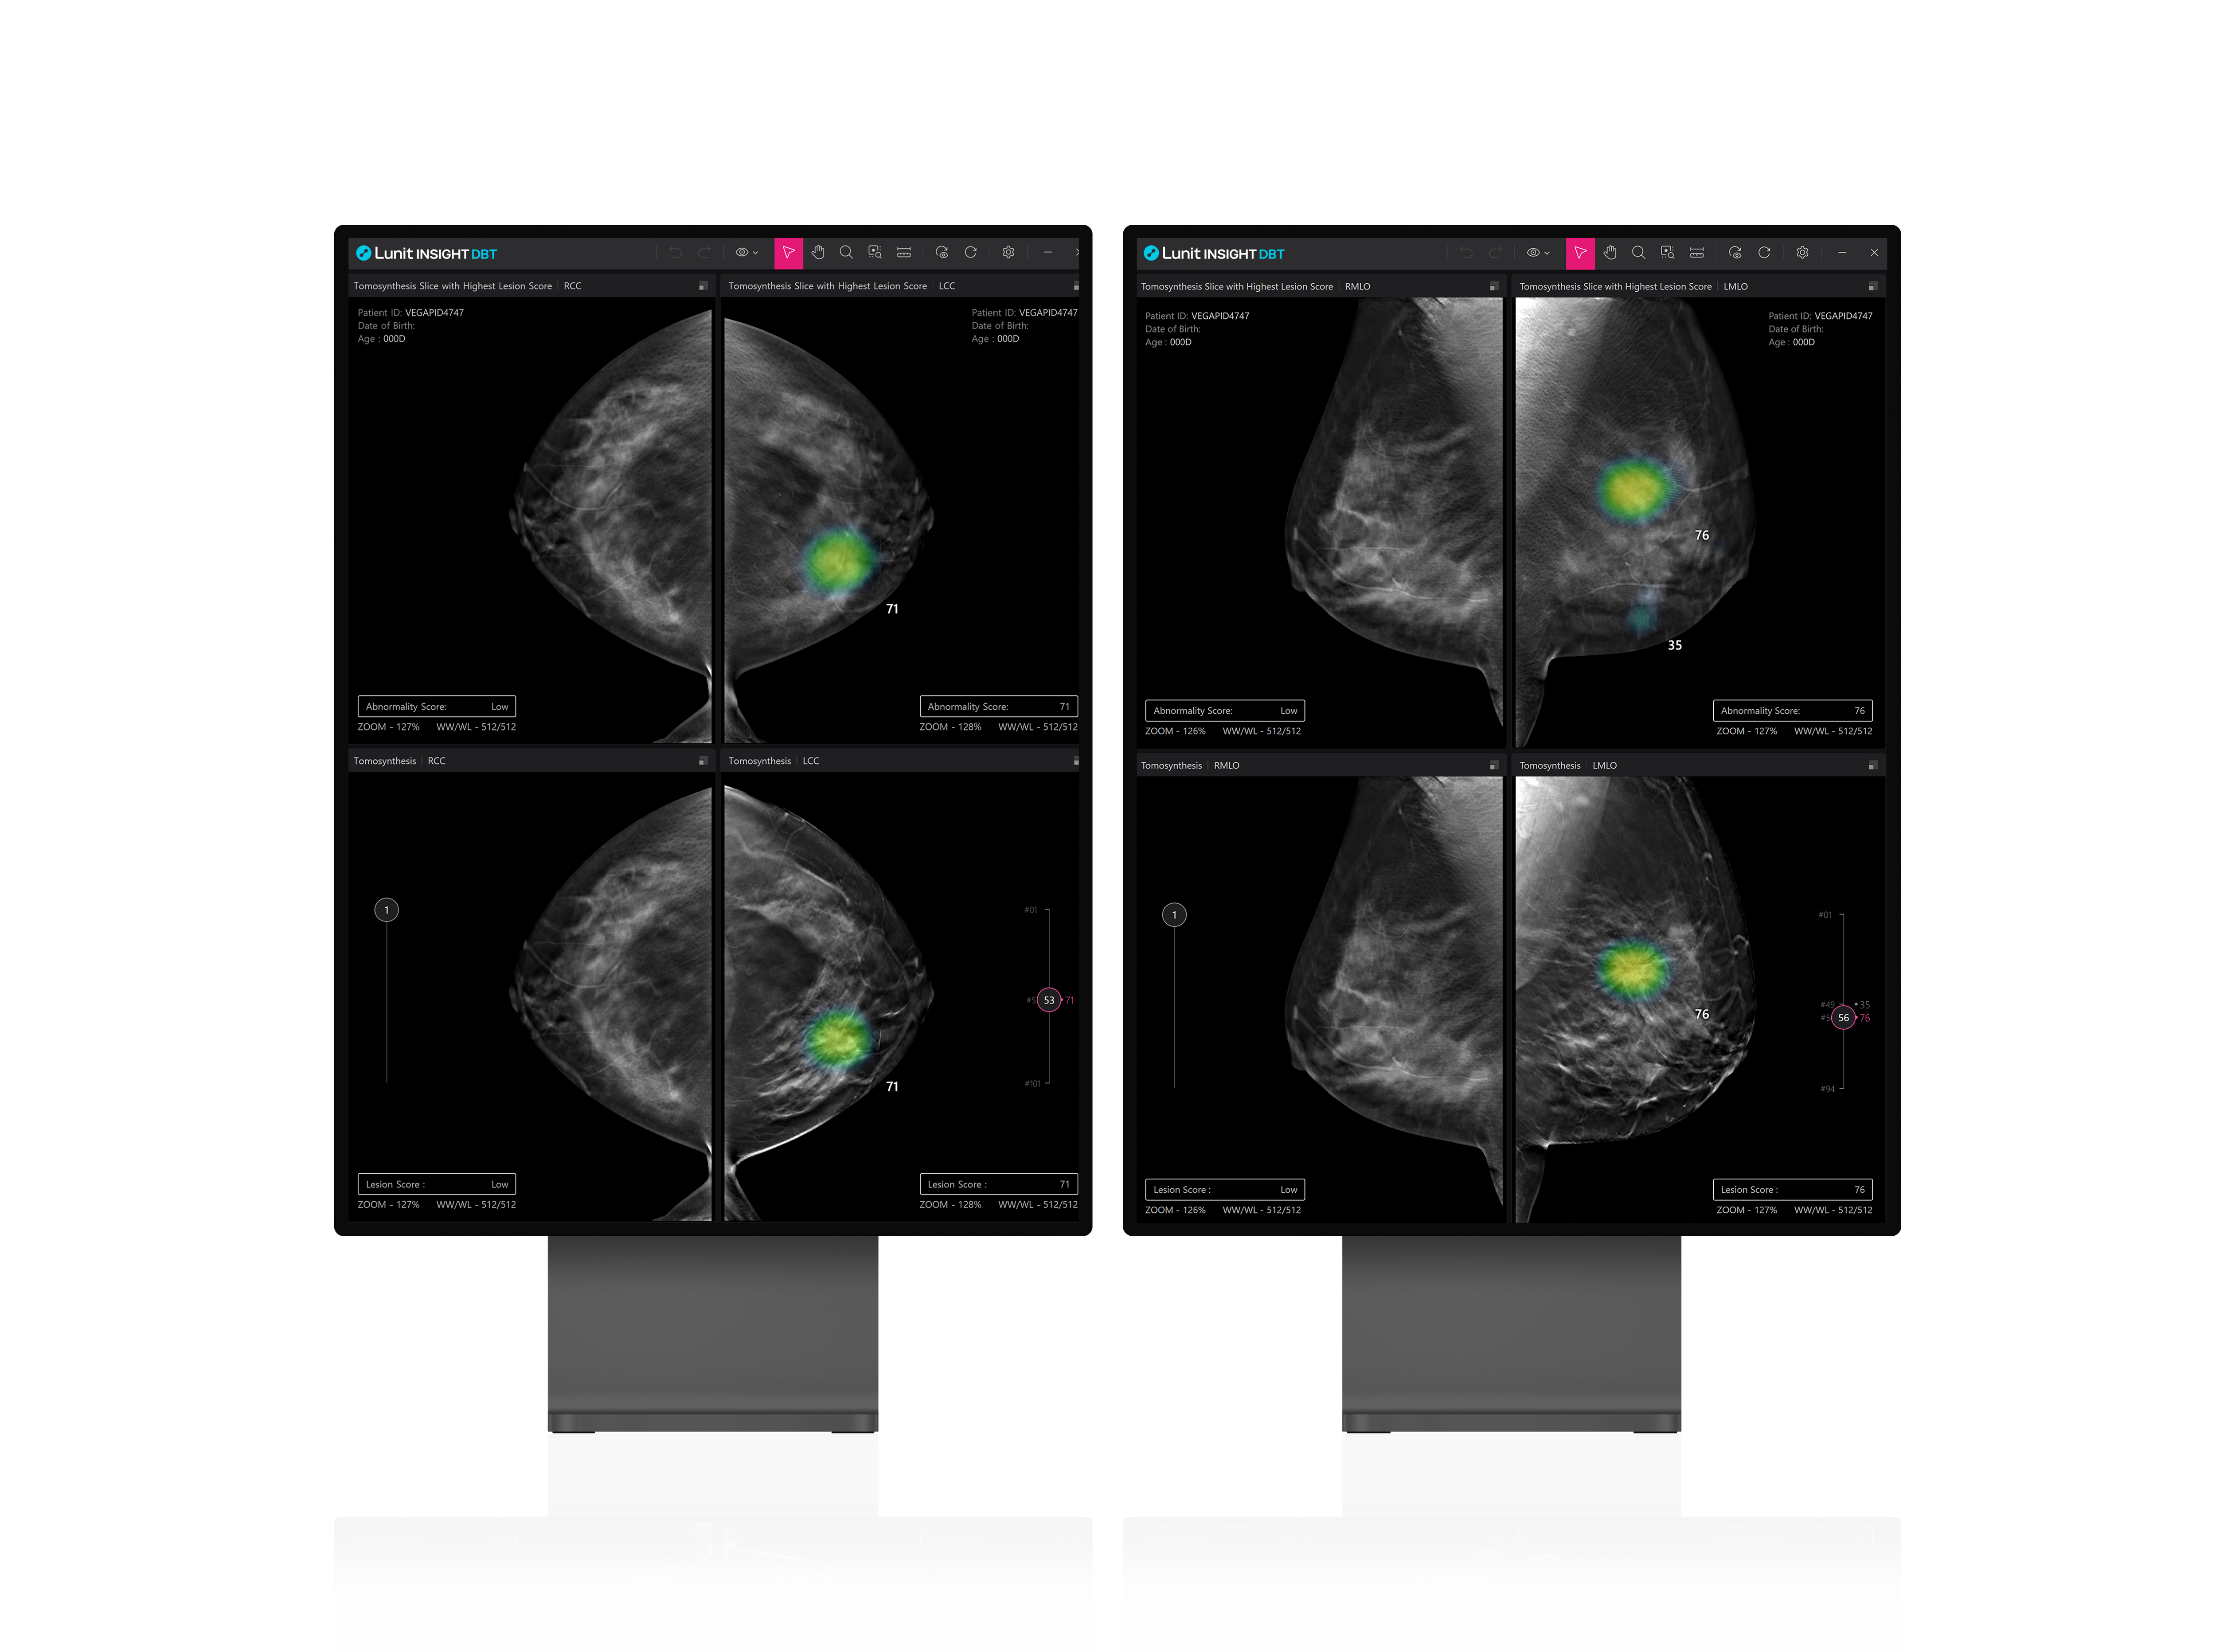

의료 인공지능(AI) 기업 루닛이 미국 테네시주 녹스빌에 위치한 유방 전문 의료기관 ‘모자이크 브레스트 이미징(Mosaic Breast Imaging, 이하 MBI)’과 유방암 검진 AI 솔루션 루닛 인사이트 DBT 및 루닛 인사이트 MMG 등 2개 제품에 대한 공급 계약을 체결했다고 29일 밝혔다.

루닛은 이번 계약을 통해 MBI에 향후 1년간 루닛 인사이트 DBT 및 루닛 인사이트 MMG를 공급하며, MBI는 이를 활용해 환자들에게 보다 정확한 유방 질환 진단을 제공하는 것은 물론 의료진의 진단 효율성을 높일 계획이다.

서범석 루닛 대표는 “의료기술 및 의료장비의 높은 전문성을 바탕으로 3차원 유방암 검진 환경이 잘 발달한 미국의 유방 이미징 센터가 FDA 승인을 갓 마친 루닛 제품을 선택한 것은 매우 고무적”이라며 “이번 공급 계약은 루닛이 루닛 인사이트 DBT를 통해 미국 시장에 진출하는 첫 단추로서, 올해 본격적으로 미국 사업 확대와 영업력 강화에 힘을 쏟을 예정”이라고 말했다.